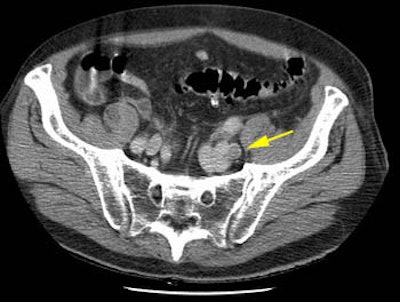

The patient shown below was post op from repair of an abdominal aortic aneurysm. The CT PE exam demonstrated emboli to the left lower lobe and right upper lobe (large clot) pulmonary arteries. The DVT portion of the exam detected clot in the left iliac vein- a finding which would not have been evident on lower extremity ultrasound. In patients that require an inferior vena caval filter the identification of clot within the iliac vessels or IVC can aid in the angiographic approach to filter placement.

A left external iliac vein clot was identified during the CT DVT exam (yellow arrow)